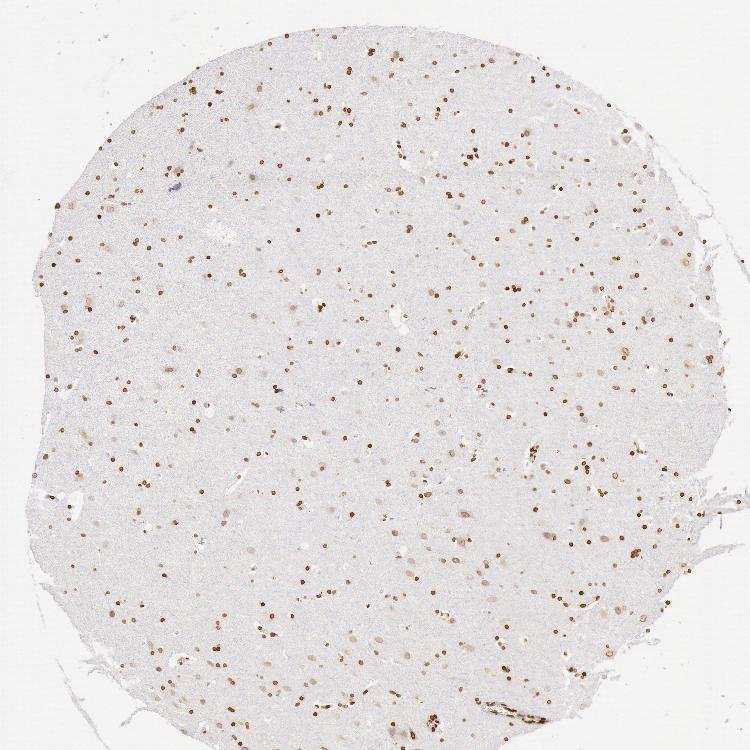

HIPPOCAMPUS - Antibody stainingi

Antibody staining in the annotated cell types in the current human tissue is reported as not detected, low, medium, or high, based on conventional immunohistochemistry profiling in selected tissues. This score is based on the combination of the staining intensity and fraction of stained cells.

Each image is clickable and will lead to virtual microscopy that enables deeper exploration of all samples and also displays staining intensity scores, fraction scores and subcellular localization as well as patient and tissue information for each sample.

Antibody HPA001209

Glial cells High

Neuronal cells High